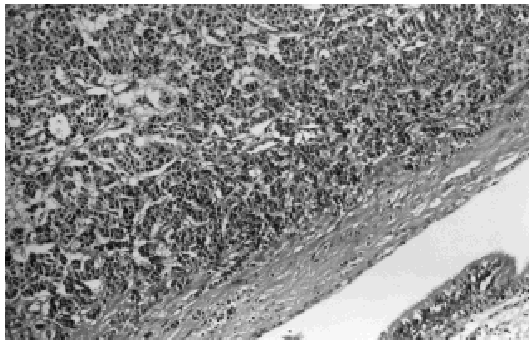

We present the case of an otherwise healthy 27-year-old woman diagnosed with a bronchial carcinoid tumor (pT1N1M0) in whom a bilobectomy (lower and middle lobes) was performed. Histology revealed a tumor composed of medium-sized polygonal cells, with slightly granular cytoplasm and round uniform nuclei, which were only slightly hyperchromatic. Mitosis was scant. These cells were organized such that the tumor presented a pattern of organoid growth (Figure). Immunohistochemistry revealed a very strong expression of chromogranin. The margin of the bronchial resection was free of neoplasia.

Figure. Normal bronchial epithelium (lower right-hand corner), with proliferation of neoplastic tissue in the bronchial airway.